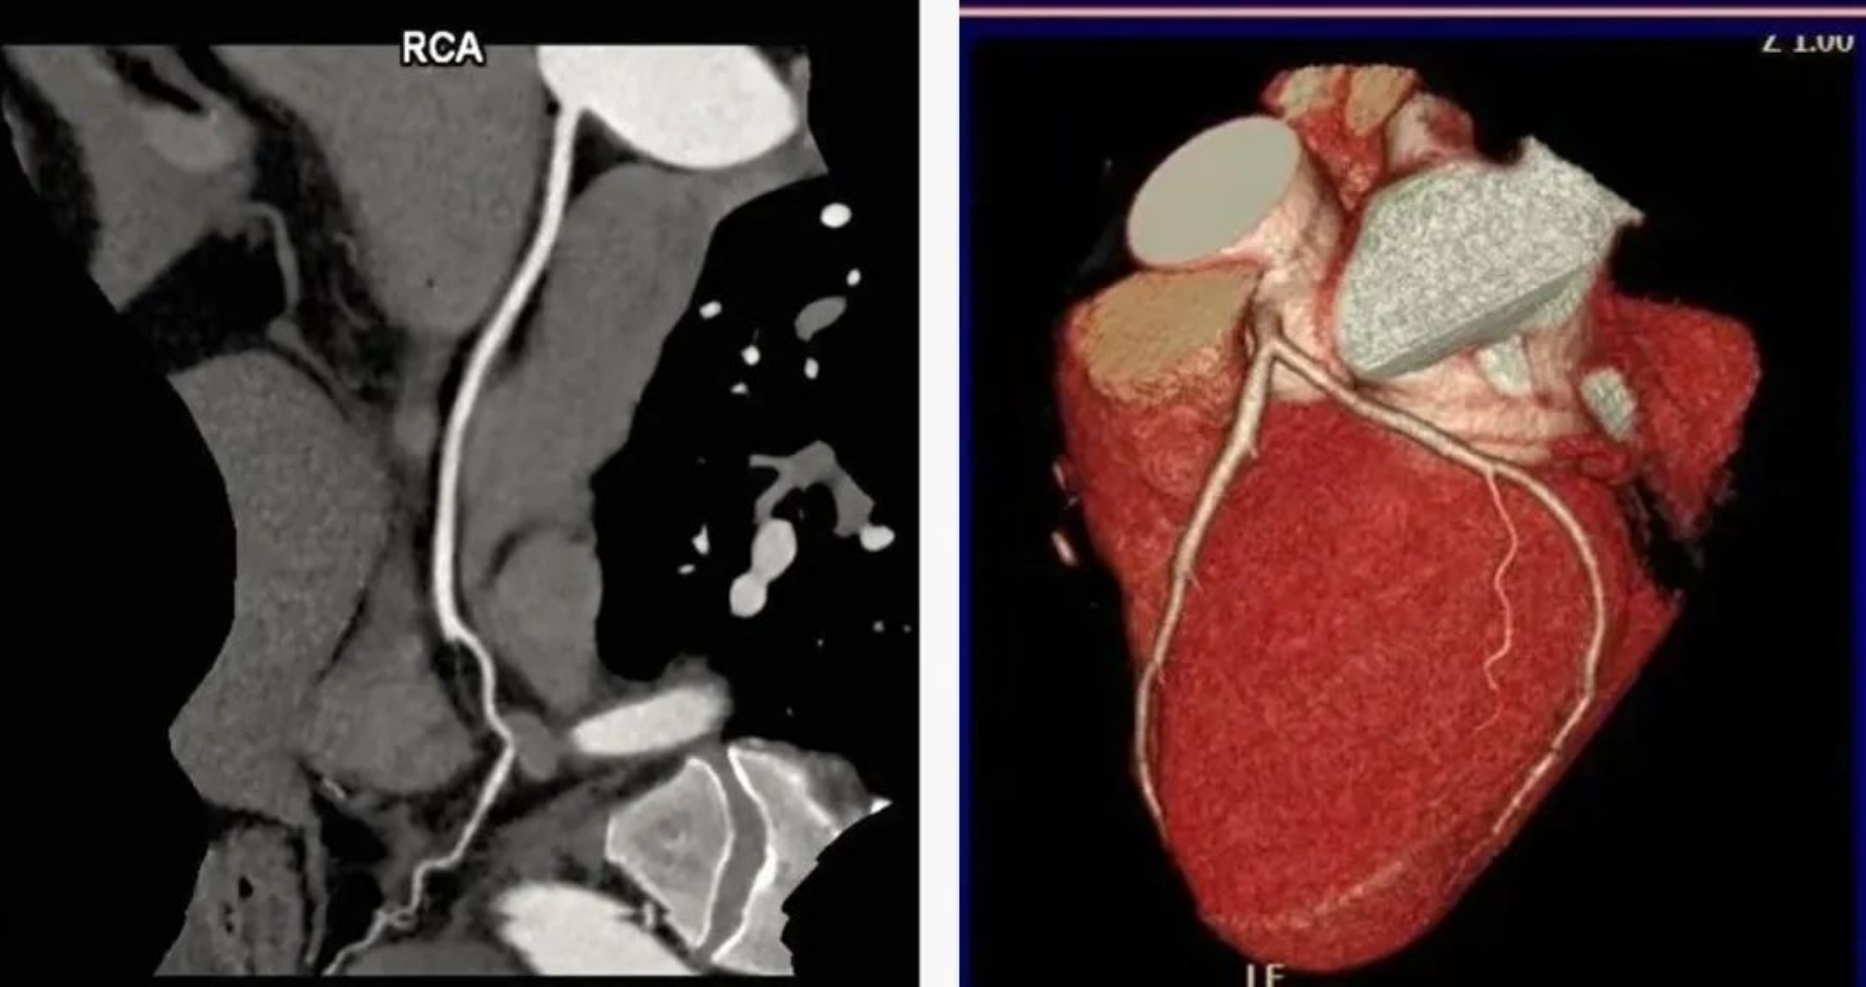

用該設(shè)備做心血管系統(tǒng)檢查,能得到對(duì)比度極佳的血管圖像。大大提高了診療的精準(zhǔn)度及工作效率,有利于醫(yī)生及早發(fā)現(xiàn)微小病灶。

通過該新型CT,不僅年老體弱的病人可以接受CT冠脈造影檢查,得到的CT圖片質(zhì)量也非常清晰,對(duì)臨床診斷的價(jià)值更大。

該設(shè)備,可以在短時(shí)間完成對(duì)冠狀動(dòng)脈缺血、肺栓塞、主動(dòng)脈瘤的一站式檢查,也可在在短時(shí)間完成對(duì)頭部血管、頸部血管、腦實(shí)質(zhì)血液灌注的一站式檢查,為腦卒中和急性胸痛患者的早期診斷和治療能力贏得黃金時(shí)間。